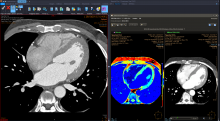

On the workflow side, several vendors are leveraging AI to pull together all of a patients' information, prior exams and reports in one location and to digest the information so it is easier for the radiologist to consume. Often the AI pulls only data and priors that relate to a specific question being asked, based on the imaging protocol used for the exam. One example of this is the Siemens Healthineers AI Clinical Pathway and Siemens AI integrations with PACS to automate measurements and advanced visualization.

There are now hundreds of AI applications that do a wide variety of analysis, from data analytics, image reconstruction, disease and anatomy identification, automating measurements and advanced visualization. The AI applications can be divided into 2 basic types — AI to improve workflow, and AI for clinical decision support, such as diagnostic aids.